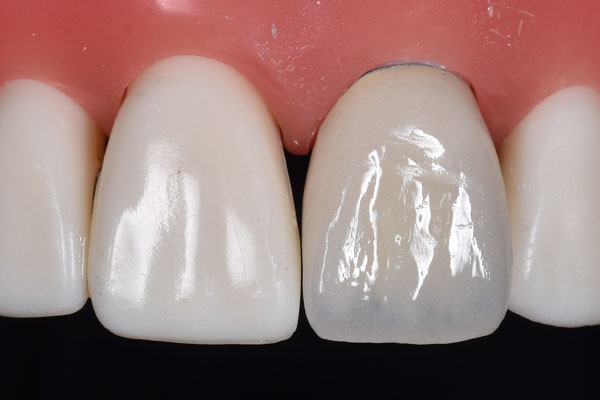

セラミックインレーは陶器の素材でできており、見た目も天然の歯と同じ色なので銀歯のようにお口の中で目立ってしまうこともなく、天然の歯と同じ透明感を再現することができ、審美的に美しい仕上がりになります。

耐久性に非常に優れた素材になっており、半永久的に使用し続けることができるといわれています。

ただし、歯ぎしりや食いしばりが強い方はまれに欠けてしまう可能性があるので、付けた後にマウスピースの装着をおすすめします。